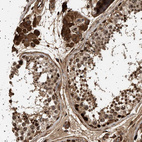

Immunohistochemical staining of human Testis shows strong granular cytoplasmic positivity in Leydig cells and cells in seminiferous ducts.